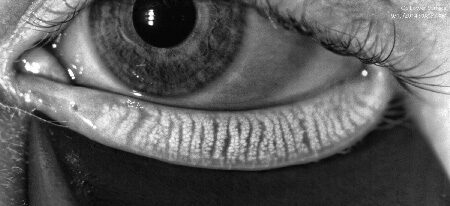

One of its standout features is the meibography function, which allows for the non-invasive imaging of the meibomian glands. These precise images enable us to accurately diagnose meibomian gland dysfunction (MGD), assess gland health, and monitor changes over time.

Meibomian glands produce the oils needed for a healthy tear film

MGD occurs when the meibomian glands become blocked. If this blockage is left untreated the glands will drop out entirely.